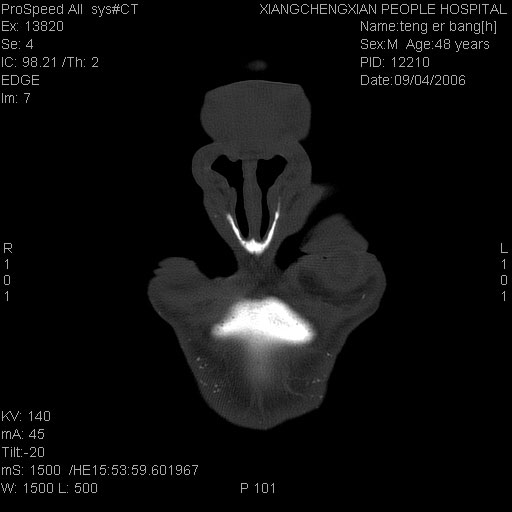

患者,男,以头面部外伤后头疼1小时为主诉入院,患者1小时前被他人打伤头部及左侧面部,眼睑无水肿,左侧面部肿胀压疼,未触及骨擦音。专科检查:耳鼻喉未见异常。

ct:平扫+冠扫:双侧鼻骨对比,冠扫s6#示右侧鼻骨尖部可见线状低密度影,边缘光滑,并见硬化.软组织未见肿胀.

诊断意见:鼻额缝(鼻骨与上颌骨额突缝),但个别同志认为是骨折.因此请同行们会诊.多谢了!